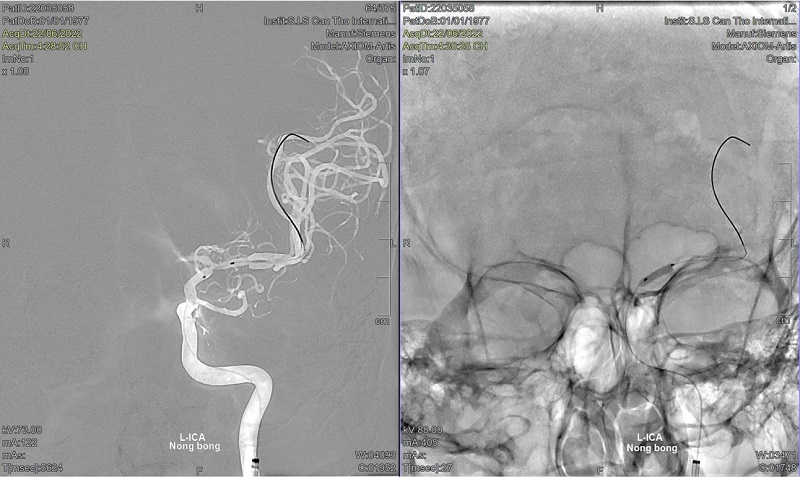

Từng có biểu hiện ngất xỉu đột ngột, ông L.M.T (Việt kiều) được bác sĩ Mỹ đánh giá là không nguy hiểm. Thế nhưng, tại bệnh viện Đa khoa Quốc tế S.I.S Cần Thơ, với công nghệ MRI 3 Tesla bác sĩ cho biết ông bị tắc, hẹp hơn 90% động mạch cảnh và được can thiệp thành công.

Một Việt kiều Mỹ yếu nhẹ nửa người, hay choáng, đang uống thuốc nhưng chưa hiệu quả bay về Việt Nam và các bác sĩ phát hiện ra bệnh hẹp động mạch cảnh nặng, nguy cơ đột quỵ.